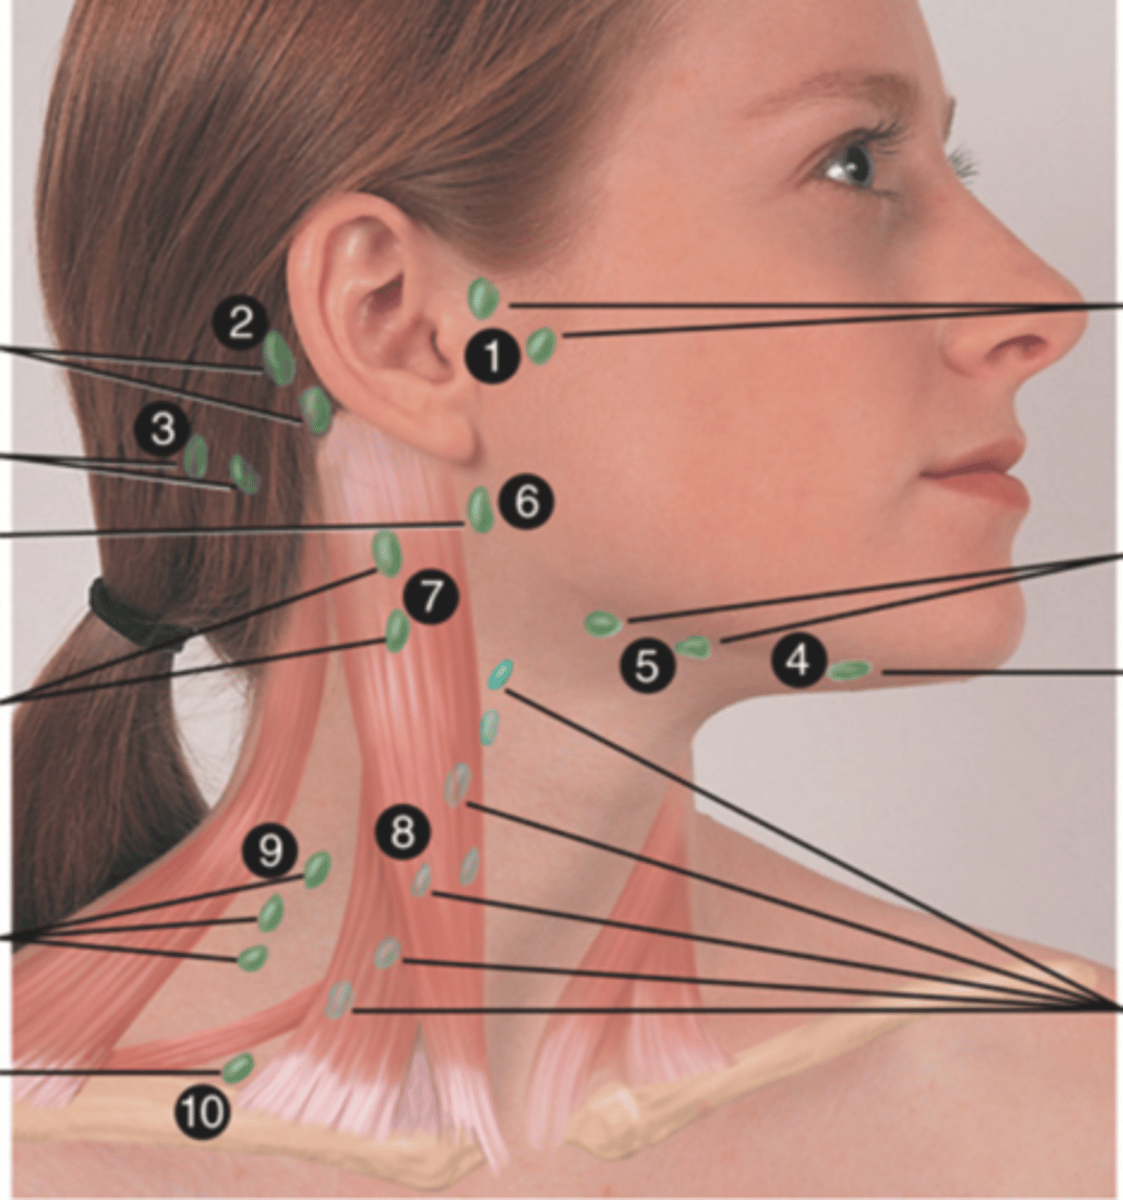

Major Lymph Nodes in the Neck (FUN!)

(Party People Often Sell Sardines Just So Dogs Pee Silver)

Preauricular Lymph Node

Lymph node in front of the ear (1)

Posterior Auricular Lymph Node

Lymph node behind the ear (2)

Occipital Lymph Node

Lymph node at the base of skull (3)

Submental Lymph Node

Lymph node under the chin (4)

Submandibular Lymph Node

Lymph node along base of mandible (5)

Jugulodigastric (Tonsil) Lymph Node

Lymph node under the angle of the mandible (6)

Superficial Cervical Lymph Node

Lymph node overlying the sternomastoid muscle (7); can feel enlarged even when there are no problems

Deep Cervical Chain Lymph Node

Lymph node located on the posterior triangle of the neck (8)

Posterior Cervical Lymph Node

Lymph node in the posterior triangle along the edge of the trapezius muscle (9)

Supraclavicular Lymph Node

Lymph node just above and behind the clavicle, at the sternomastoid muscle (10)